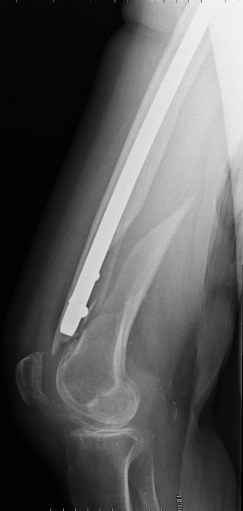

4. We could treat this fracture like there is no a nail - new locking plates allow for secure fixation.... two similar cases are attached...

Images sent by Professor Kanlic look nice, very good job. Excellent achorage in distal fragment. However, unicortical screwing or bicortical

makes a difference, also for locked screws. Proximal fragment unicortical fixation may present stability not easlily predictable. Certainly its stability for wheelchair should be sufficient. Full weight bearing can not be mentioned for this case. If minimal bearing is allowed full weight

single step may happen in elderly.

Gamma nail exchange may probably fit the criteria of optimal and minimal invasivness, indeed. Removal could be relatively fast due to large intramedullary diameter seen on X-ray.

I do agree that distal locking of the nail in distal femur remains critical.

Our experience with locking plates in osteoporoticbone and weight bearing is that there's no difference with a nail. the old patient start walking with crutches and 20kg weight bearing as the general conditions are good as for the nail. In this case 13 holes LISS with at least 8 cortex proximally

Dear Sir, in my opinion it's better to take off the gamma nail, anatomically reduce the spiral with 2 lag screws, and fix the shaft fracture with a LISS-LCP 13 holes. No bone graft. Immediate mobilization and weight bearing.